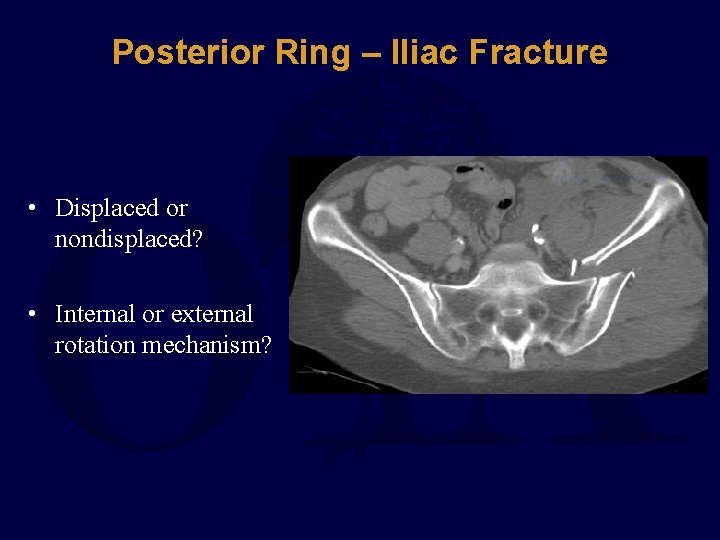

Posterior Ring – Iliac Fracture • Displaced or nondisplaced? • Internal or external rotation mechanism?